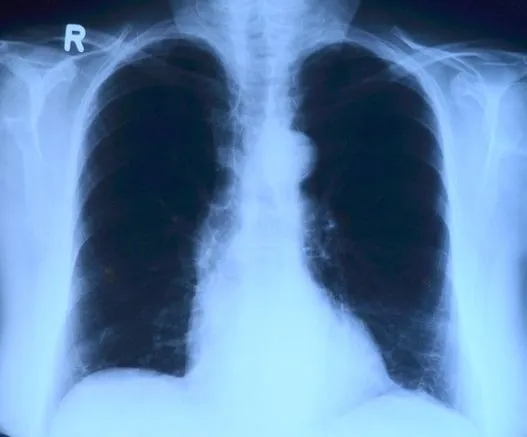

Районная больница Валдгейма принимает до 70 пациентов в день, а областная больница Биробиджана выручает коллег кадрами. Врачи констатируют, что среди обследуемых есть случаи заболевания пневмонией. Медработники предупреждают, что пренебрегать обследованием лёгких не стоит, флюорографию нужно проходить регулярно – один раз в год.